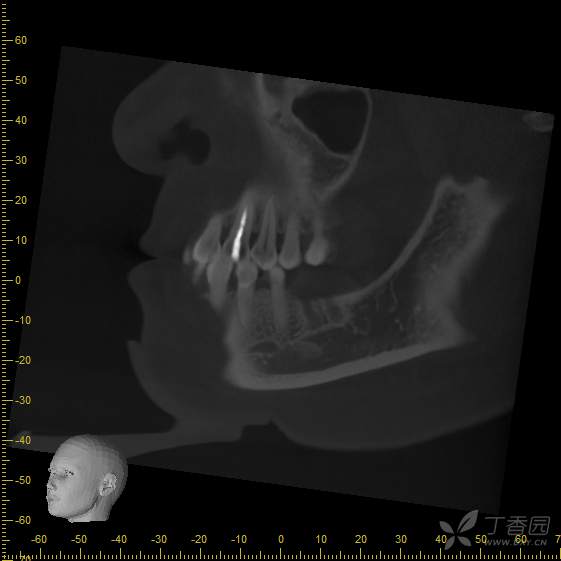

手术即刻拍摄cbct,手术过程中刮净肉芽组织,碘酊灼烧,大量生理盐水冲洗,植入4.8*8mm骨水平种植体一枚

手术后3个月,可见种植体周围骨结合良好,行软组织成形(即二期),局麻下更换愈合帽。